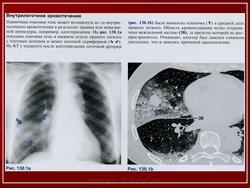

Лёгочная геморрагия.